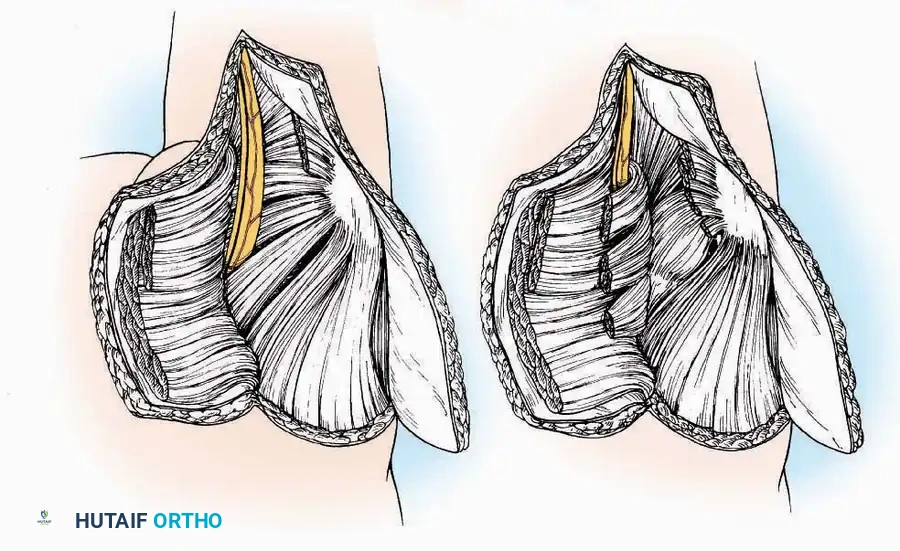

U Approach

Indications: Extensive plantar fasciotomy, radical tumor resection, or complex osteomyelitis debridement requiring access to the entire plantar surface of the calcaneus.

Positioning: Prone, with the leg supported on a large sandbag.

Surgical Technique:

* Incision: Join the medial and lateral approaches described above to form a large, continuous U-shaped incision around the posterior four-fifths of the calcaneus.

* Flap Elevation: Deepen the incision directly to bone. Elevate a massive plantar flap consisting of skin, the specialized fatty heel pad, and the plantar fascia. Retract this flap distally to expose the entire plantar calcaneal tuberosity.

Kocher Approach (Curved L)

Indications: Complete excision of the calcaneus (calcanectomy) for malignant tumors or recalcitrant osteomyelitis.

Surgical Technique:

* Incision: Incise the skin over the medial border of the Achilles tendon, starting 7.5 cm proximal to the calcaneal tuberosity. Extend it distally to the inferoposterior aspect of the tuberosity, curve it transversely around the posterior heel, and continue distally along the lateral surface of the foot to the tuberosity of the fifth metatarsal.

* Deep Dissection: Divide the Achilles tendon directly at its insertion and carry the dissection down to the bone.

* Enucleation: To reach the superior surface, free all tissues beneath the severed Achilles tendon. The calcaneus can then be enucleated subperiosteally or extraperiosteally depending on the oncologic or infectious margins required.